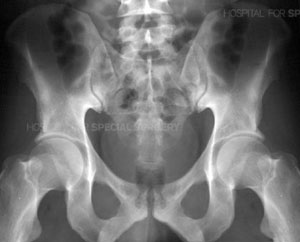

We finally know what the cause of the pain is. It’s not a torn leg muscle or groin injury. He went for an x-ray and as clear as daylight, he has a stress fracture of his pelvis.

Pelvis

Photo credit: Google image (not KK’s)